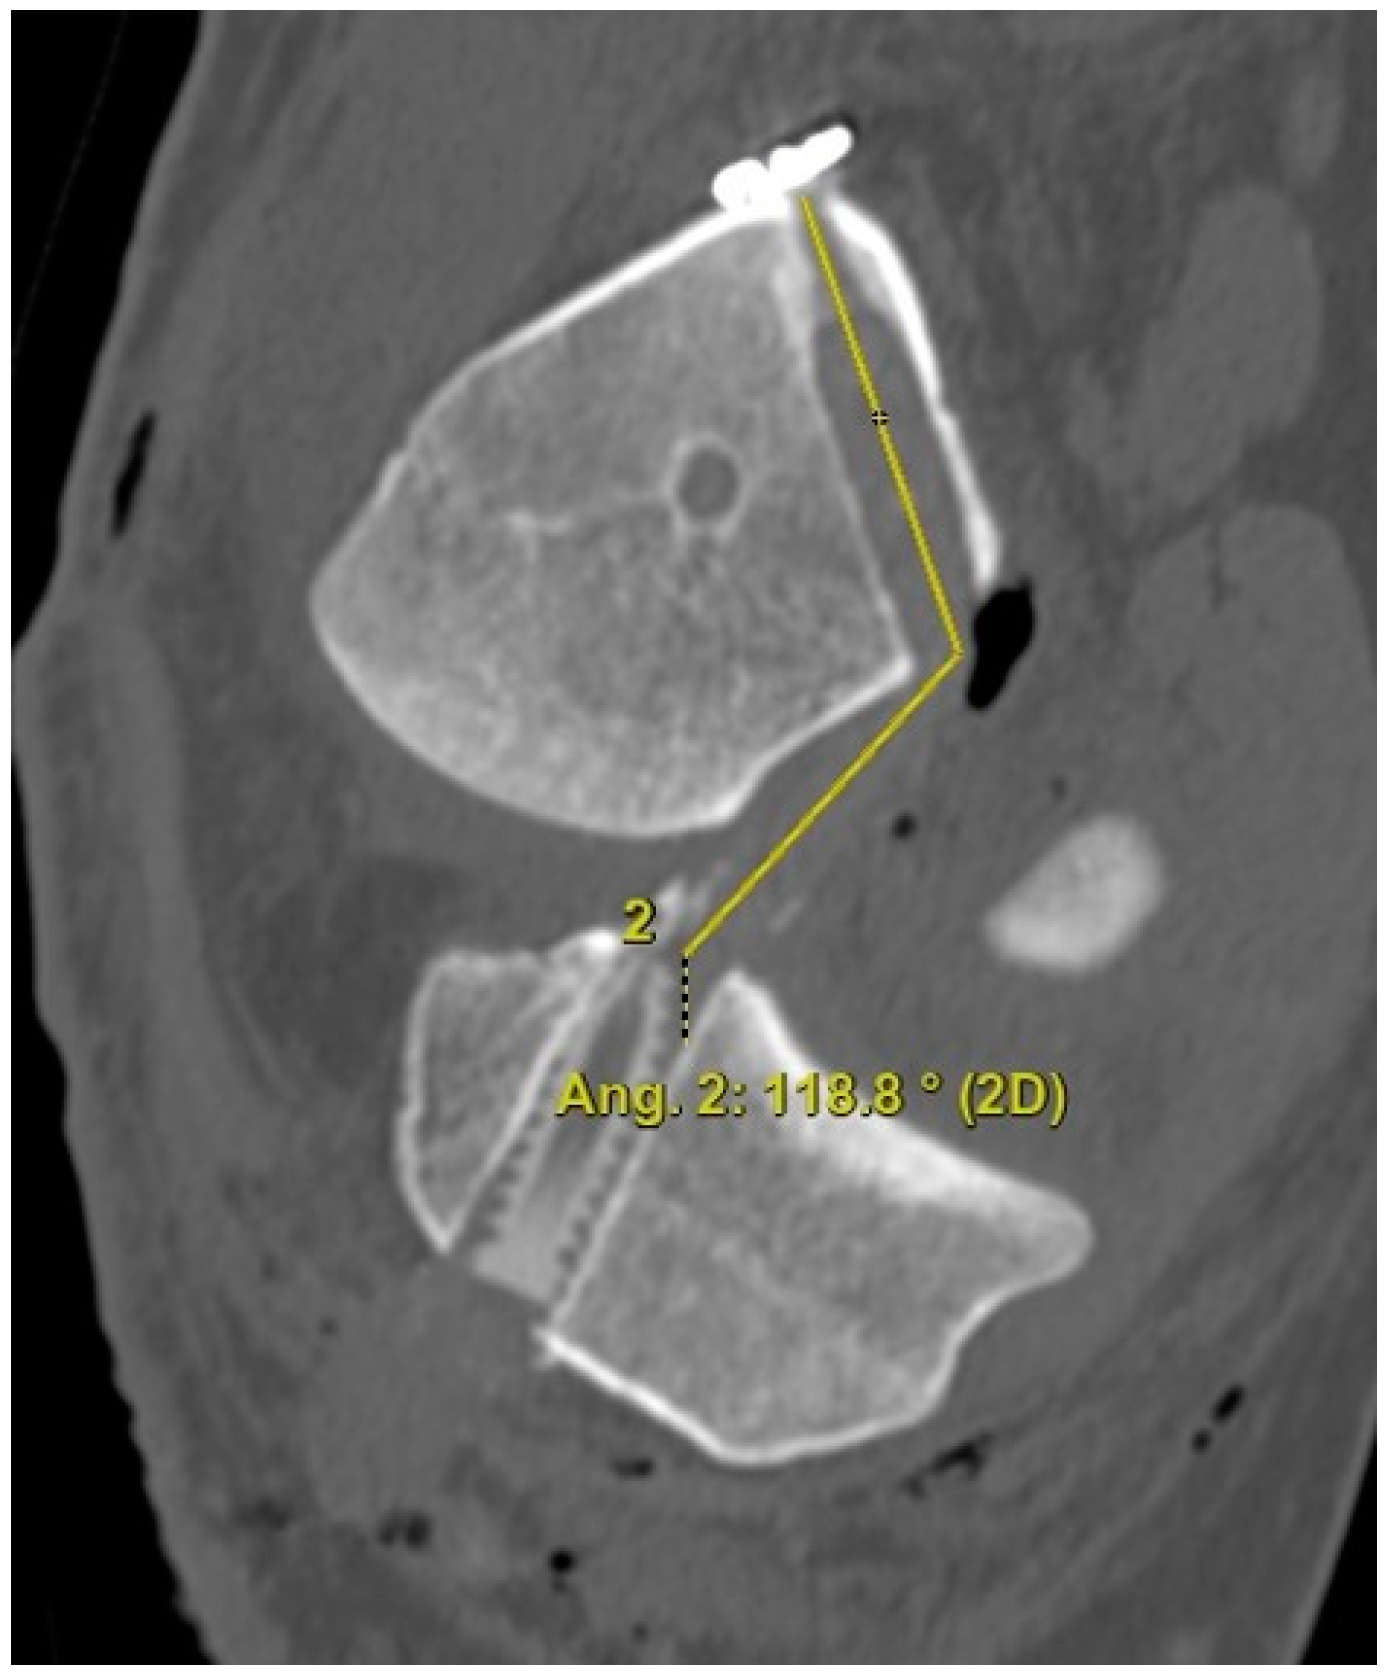

The 3D CT scans were imported into 3D software (AW Sever 3.2 PACS system, GE Healthcare; Chicago, IL, USA) for the assessments of the femoral graft bending angle and femoral tunnel length. The femoral graft bending angle was defined as the angle formed by the longitudinal axis of the femoral tunnel and the line connecting the intra-articular aperture of the tibial tunnel and the intra-articular aperture of the femoral tunnel (Figure 3). The femoral tunnel length was defined as the distance between the center of the extra-articular aperture of the femoral tunnel and the center of the intra-articular aperture of the femoral tunnel in a plane where the entire femoral tunnel could be viewed (Figure 4). Posterior wall breakage of the femoral tunnel was also checked.

Figure 3. The femoral graft bending angle is defined as the angle formed by the longitudinal axis of the femoral tunnel and the line connecting the intra-articular aperture of the tibial tunnel and the intra-articular aperture of the femoral tunnel.